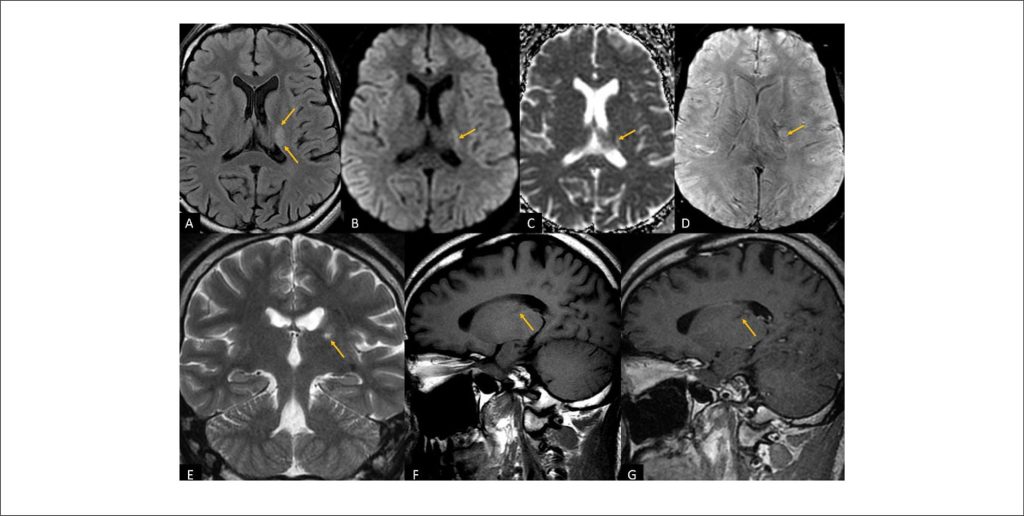

Ischemic Stroke in a Young Adult: a diagnostic challenge. Exploring the association between Patent Foramen Ovale and Chiari Network

Globally, strokes are the second leading cause of mortality,, and are broadly categorized into hemorrhagic and ischemic types., In 2019, ischemic stroke accounted for 62.4% of all cases, totaling 7.63 million episodes. Projections indicate a substantial increase in stroke prevalence, from 3.9% in 2020 to an estimated 6.4% by 2050. Despite comprehensive etiological investigations, the underlying cause of cerebrovascular ischemic events remains undefined in 10% to 40% of the cases, known as cryptogenic stroke.

Stroke is often a disabling condition and poses a major threat to the socioeconomic stability of a country, particularly in developing nations. The incidence of ischemic stroke has been increasing, particularly among individuals under 55 years of age. Approximately 10% to 15% of all strokes manifest in young adults aged 18 to 49., This trend underscores the critical importance of stroke prevention strategies, even within this younger demographic.